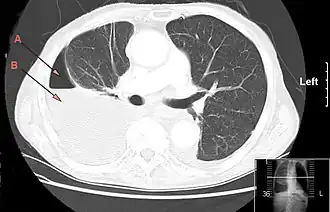

CT-thorax laat een grote rechtszijdige hydro-pneumothorax zien, ontstaan door empyeem.

Pijl A: lucht, B: vocht | ||||